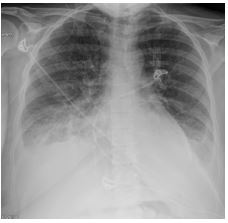

A 29-year-old primigravid woman with history of systemic lupus erythematosus, managed with hydroxychloroquine, and no previous cardiac history was admitted for concern of preterm labor with dichorionic/diamniotic twin pregnancy at 32 weeks and 2 days. Preterm labor was arrested at 0.5 cm during first day of admission. Antenatal steroids were given ongoing symptomatic contractions. She started to have progressive dyspnea and had decreased oxygen saturation of 94%. Upon work up, there was no evidence of an infectious etiology. A chest x-ray showed moderate to severe pulmonary edema and cardiomegaly (Figure 1). Electrocardiograph showed sinus tachycardia. On presentation, her echocardiogram showed moderate to severe eccentric mitral regurgitation, a right atrial pressure of 20 mmHg and an EF of 62% (Figure 2). There was no evidence of mitral valve prolapse. LA size and biventricular size were preserved. Rheumatology was consulted during her inpatient stay, and felt that this was unlikely a lupus flare or Libman-Sacks endocarditis and instead was diagnosed with worsening peripartum cardiomyopathy. Repeat echocardiogram was performed 24 hours after initial echocardiogram and showed severe mitral regurgitation and worsening ejection fraction of 50.4% (Figure 2).

Figure 1: A chest x-ray during third day of admission showing bilateral pleural effusions